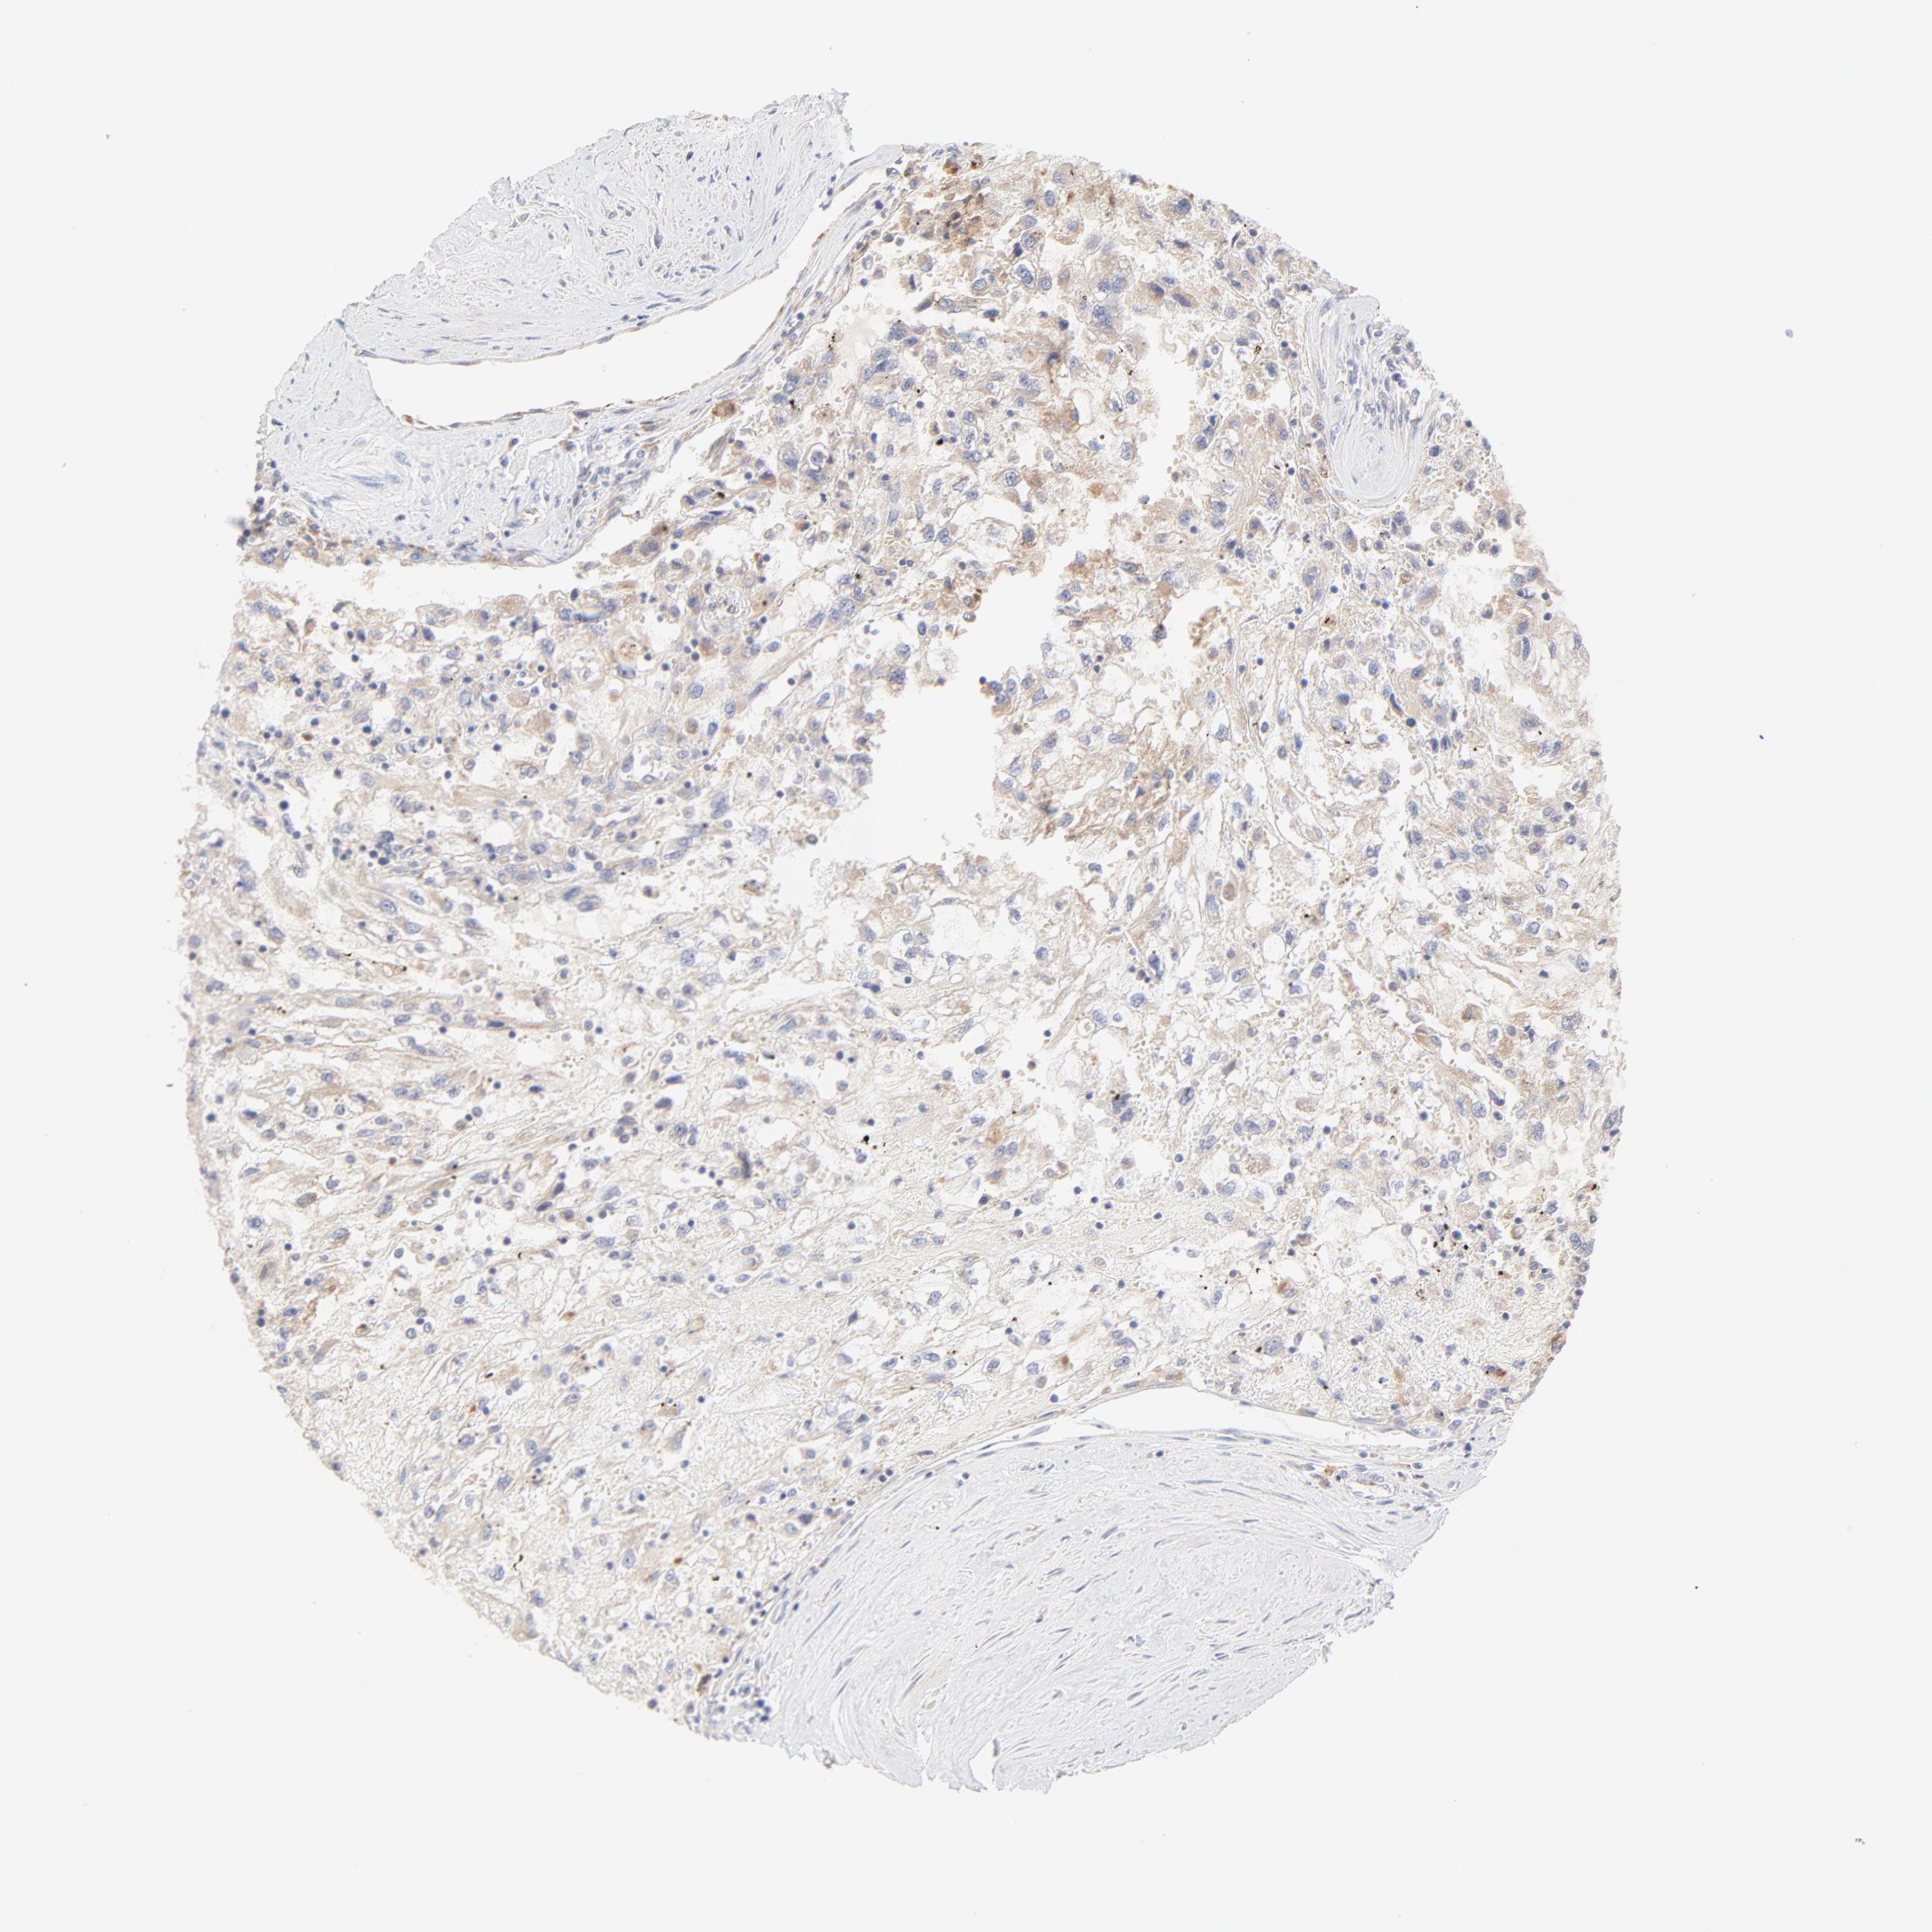

KIDNEY RENAL CLEAR CELL CARCINOMA (VALIDATION) - Interactive survival scatter ploti

The Survival Scatter plot shows the clinical status (i.e. dead or alive) for all individuals in the patient cohort, based on the same data that underlies the corresponding Kaplan-Meier plots. Patients that are alive at last time for follow-up are shown in blue and patients who have died during the study are shown in red.

The x-axis shows the expression levels (FPKM) of the investigated gene in the tumor tissue at the time of diagnosis. The y-axis shows the follow-up time after diagnosis (years). Both axes are complimented with kernel density curves demonstrating the data density over the axes. The top density plot shows the expression levels (FPKM) distribution among dead (red) and alive patients (blue). The right density plot shows the data density of the survived years of dead patients with high and low expression levels respectively, stratified using the cutoff indicated by the vertical dashed line through the Survival Scatter plot. This cutoff is automatically defined based on the FPKM cutoff that minimizes the p-score. The cutoff can be changed by dragging the vertical line or by entering a cutoff value in the square labeled "Current cut-off".

Under the Survival Scatter plot the p-score landscape (black curve; left axis) is shown together with dead median separation (red curve; right axis). Dead median separation is the difference in median mRNA expression between patients who have died with high and low expression, respectively. It is calculated as follows: median FPKM expression of dead patients with high expression - median FPKM expression of dead patients with low expression. This is intended to aid the user in visually exploring custom cutoffs and the associated p-scores and dead median separation.

Individual patient data is displayed and can be filtered by clicking on one or more of the category buttons on the top of the page. Categories describing expression level and patient information include: high, low, alive, dead, female, male and tumor stages. The scale of the x-axis can be toggled between linear and log-scale by clicking on the "x log" button. Mouse-over function shows TCGA ID, patient information and mRNA expression (FPKM) for each patient.

& Survival analysisi

Kaplan-Meier plots summarize results from analysis of correlation between mRNA expression level and patient survival. Patients were divided based on level of expression into one of the two groups "low" (under cut off) or "high" (over cut off). X-axis shows time for survival (years) and y-axis shows the probability of survival, where 1.0 corresponds to 100 percent.

MTERF2 is not prognostic in Kidney Renal Clear Cell Carcinoma (validation)

: 13.76

Average pTPM 16.9

Number of samples 100